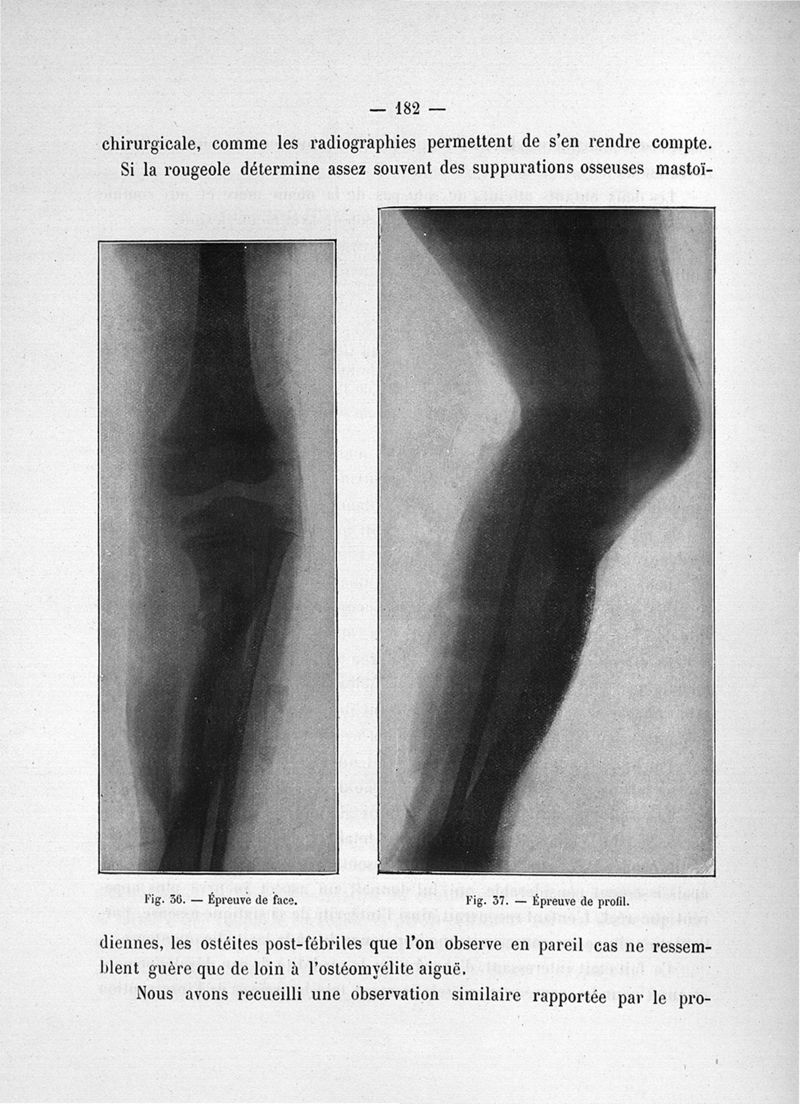

Teissier, Pierre.

Titres et travaux scientifiques

Paris, Masson et Cie, 1918.